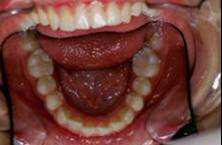

Je crois cette fois ca va marcher. Il s'agit d'une jeune fille de 12 ans, origine franco-libanaise, deja reglee depuis qqs mois. Classe II1 dentaire. Une demande majeure pour la patiente et sa maman: Les dents du haut sont trop en avant, il ne faut surtout pas les avancer ou les garder comme ca!!!

Merci pour tous ces messages qui montrent que vous estes tous sensibles a cette retrogenie, et surtout votre concepte anti-extraction. Figurez vous et c'etait exactement mon point de vu de depart car j'ai pris ce cas comme un type caucasien, europeen et j'ai fait le deverrouillage necessaire sous toutes ses formes mais la mandibule n'a pas voulu avancer du tout, meme pas un mm!! Je crois que la typologie ethnique, sagittal et vertical, de cette patiente ne permettait pas l'avancement mandibulaire par contre l'avancement alveolaire, bonjour les degats!!!!! Une autre difference, dans un pays chaud une fille de 12 ans c'est comme une fille de 14 ans dans un pays froid, il ne faut pas fantasmer sur ce que je dits mais c'est la verite?!!

Voici les photos intermediaire apres: un QH, reeducation,propuleur Balters simple, multi-bague avec el II ancrage maxi bas, mini haut avec le trace. La maman et la patiente n'etaient pas d'accord du tout! Je comprends tout a fait leur point de vue... A suivre